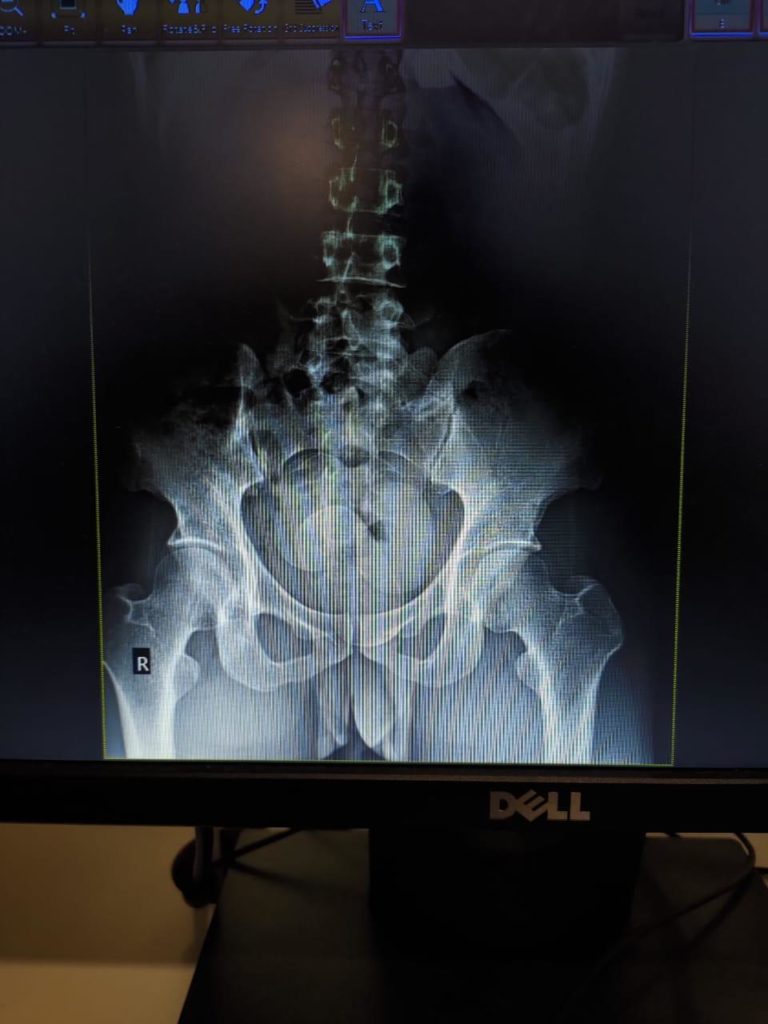

“Pemeriksaan barang bawaan penumpang tidak mendapatkan hasil, maka dilakukan pemeriksaan badan. Dan untuk itu petugas Bea Cukai Batam membawa penumpang tersebut ke Rumah Sakit Awal Bros untuk dilakukan Rontgen,” sambungnya.

Sumarna menyebut, setelah dilakukan Rontgen kedapatan 3 benda asing menyerupai kapsul nampak pada citra rontgen yang diduga NPP disimpan dalam dubur penumpang tsb.

“Tersangka kemudian dibawa ke KPU Bea dan Cukai Batam untuk dilakukan pemeriksaan mendalam dan didapati bahwa 3 kapsul tersebut adalah Sabu (Methamphetamine) sebanyak 303 gram,” paparnya.